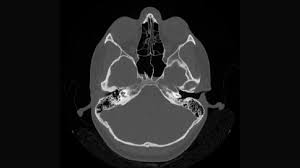

A Sinus CT Scan offers a detailed view of the sinus cavities, revealing blockages, infections, or structural abnormalities that traditional X-rays might miss. For Anjali, this meant finally understanding the root cause of her chronic sinus infections – a deviated septum and nasal polyps. With this information in hand, her doctor was able to craft a personalized treatment plan, which included a minimally invasive surgery followed by appropriate medication, leading to significant improvements in her symptoms.